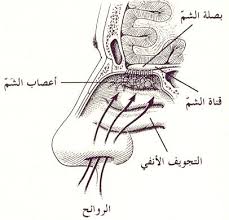

الانف